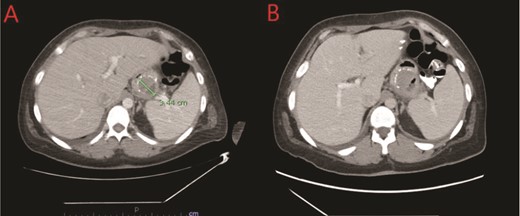

We report a case of a 39-year-old female, with a past medical history significant for morbid obesity status-post SADI-S ⁓3 years prior at an out-of-state medical center who was transferred to our institution with computed tomography (CT) evidence of an intramural abscess near the proximal greater curvature of the stomach as displayed in Fig. 1A. Our patient had a reported weight loss of 99.8 kg since her bariatric surgery and did not encounter any significant issues until this current episode of symptoms began. She was previously treated with a 2-week course of intravenous (IV) antibiotics with minimal symptomatic improvement prior to transfer to our facility. Notably, the patient was treated with oral corticosteroids ⁓1 month before she initially presented to the hospital for a streptococcal infection. She reported being a non-smoker (neither currently nor previously) and also denied recent use of NSAIDs or proton pump inhibitors (PPIs).

(A) CT showing a complex fluid collection at the proximal greater curvature of the stomach consistent with intramural abscess. (B) Interval improvement in complex fluid collection after endoscopic stent removal.